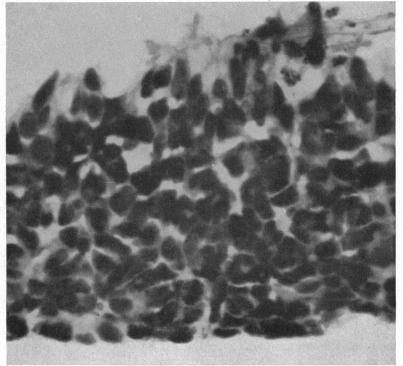

Diffuse infiltrating retinoblastoma.

Br J Ophthalmol. 1960 Jan;44(1):35-41. doi: 10.1136/bjo.44.1.35.